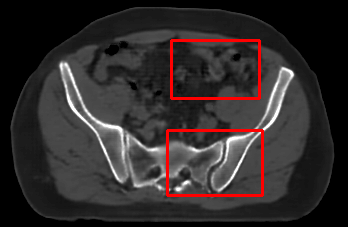

In the MRI CT translation in the Gold Atlas dataset (Fig. 8), major bones and muscles are translated faithfully. Yet, diffusion sampling leads to some inaccuracies in the outline of bones and hallucinations of the textures of inner organs. Conversely, regression sampling faithfully translates bones while still blurring the inner organs and generating artifacts. This indicates that rendering CTs is under-defined by the given MRI guidance alone.

In the quantitative analysis (Tab. 3), we found a slightly increased performance of sampling with over regression sampling in terms of PSNR and accuracy of the downstream task. As performance gains are marginal and the assessment is based on few () test cases, we still assume the performance of diffusion and regression to be similar.

Diffusion sampling YODA results in hallucinated organ shapes and textures that smoothen out and disappear when increasing the in Exp sampling or when using regression sampling. Regression sampling creates some artifacts. Note that, for all methods, the translation quality for inner organs is rather poor, whereas bone and muscle translation is reliable.

When benchmarking on the more heterogeneous and lower-quality BraTS dataset (Tab. 2, left), regression sampling of YODA achieved significantly better images than all competing methods in terms of PSNR, SSIM, and downstream glioma segmentation. Similar results were obtained in the IXI dataset (Tab. 2, right), where YODA significantly outperformed all competing methods in SSIM and PSNR. In the full-brain segmentation conducted from the synthetic images, YODA’s images were significantly better than all competing methods in at least either the Dice score or the HD. In the MRI CT task on the small pelvic dataset, regression and ExpA sampling achieved the highest SSIM, whereas the DB of Choo et al. [31] had the highest PSNR. Both, regression and ExpA sampling YODA also performed competitively in the downstream segmentation task. Note that, for all methods, the translation of inner organs was rather poor and included either texture hallucination (ResViT, I2I-Mamba, diffusion-sampling YODA) or an over-smooth image appearance (Choo et al. [31], SelfRDB, SynDiff, ExpA and regression sampling YODA, Fig. 8).